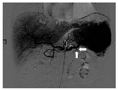

入院后予输注悬浮红细胞、抑酸护胃、补铁等治疗,患者未再出现呕血、黑便,大便隐血试验阴性。胃镜检查示十二指肠乳头处活动性渗血(图2)。腹部增强MRI检查示:①轻度肝硬化,轻度脂肪肝,动脉期肝脏异常强化灶,考虑异常灌注,左肝小囊肿。②脾大,脾部分梗死考虑,脾静脉显示不清,胃前方侧支形成;脾静脉与肠系膜上静脉汇合处血栓形成可能;脾动脉瘤。③考虑慢性胰腺炎。④胆囊底壁稍厚,胆囊腺肌症可能;右肾小囊肿。遂在介入科行脾动脉瘤栓塞术。术中见脾动脉局部囊袋样凸起,直径约8 mm,未见明显造影剂外溢,使用可控弹簧钢圈和栓塞胶进行栓塞(图3)。术后造影检查显示脾动脉主干及其远端分支显影良好,脾动脉瘤未见确切显示。患者术后多次复查血常规,血红蛋白水平维持在90 g/L以上。后复查胃镜示十二指肠乳头仍有活动性出血。遂行超声胃镜检查,内镜下见胃底、胃体上段多条曲张静脉,部分成团、成球样改变(图4A);十二指肠乳头结构无特殊,其开口可见墨绿色胆汁溢出;超声胃镜检查见胰腺实质回声不均匀,散在较密集点片状高回声区,呈云朵样;胰管显示,管壁回声增粗、增强;胆总管显示,胰头段胆管壁增厚;胰腺尾部见一3.0 cm×1.9 cm无回声区(图4B),部分囊壁呈片状增厚;脾脏显示增厚。诊断:慢性胰腺炎;胰尾部囊性病变,性质待定;重度胃底静脉曲张。对症支持治疗后患者未再解黑便,复查血红蛋白水平稳定,患者拒绝进一步检查,要求出院随访。

2018年2月11日,患者因"再发黑便1周"再次入住浙江大学医学院附属邵逸夫医院消化内科。查血常规示红细胞计数为1.84×1012/L,血红蛋白为34 g/L,平均红细胞体积为65.9 fL,平均血红蛋白水平为279 g/L。胃镜检查示十二指肠乳头搏动性出血,中重度胃底静脉曲张。胃镜下乳头冲洗后间断可见黄绿色胆汁流出,考虑胰管来源出血可能性大。急诊腹部增强CT检查示脾动脉瘤复发,行急诊脾动脉造影术和脾动脉栓塞术,脾动脉局部可见造影剂外溢,考虑活动性出血(图5);超选栓塞后造影见破裂口处闭塞,远端脾动脉通过侧支部分代偿,术中证实为脾动脉瘤破裂入胰管引起消化道出血。病情稳定后出院,随访5个月患者未再发呕血、黑便,复查血红蛋白水平在正常参考值范围内,大便隐血阴性。